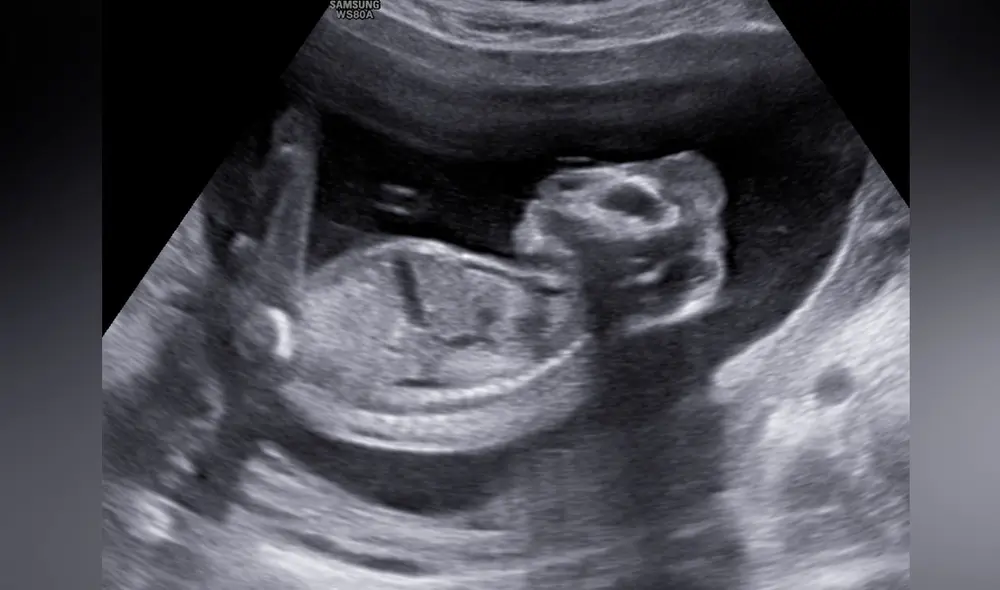

“Es doloroso saber que daré a luz para enterrarlo”, señaló Davis, quien se enteró del problema cuando se sometió a su primera ecografía a las 10 semanas de embarazo en el Woman’s Hospital, Louisiana.

“El ultrasonido resultó anormal, se dieron cuenta de que al bebé le faltaba la parte superior de la cabeza y una parte del cráneo, la parte de arriba del cráneo no se había formado”, añadió al medio local WAFB.

El diagnóstico de los médicos fue de una anencefalia, una malformación genética en que el feto nace sin partes del encéfalo y el cráneo, no sobreviven más de unos minutos u horas, según los Centros para el Control y Prevención de Enfermedades (CDC).